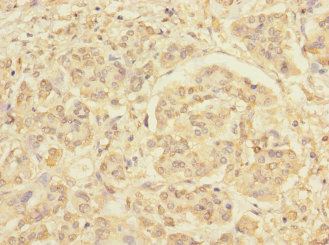

Immunohistochemistry of paraffin-embedded human pancreatic cancer using CSB-PA873646DSR1HU at dilution of 1:100